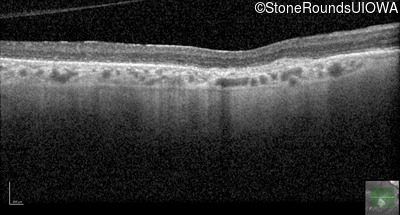

Optical Coherence Tomography - Right - 20/100

Exemplar / OCT Stack